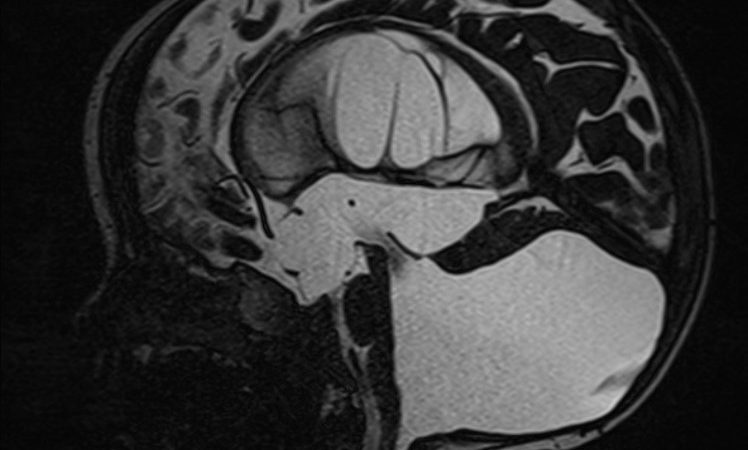

Dandy Walker Syndrome Article topic: Dandy Walker Syndrome Author: Ghayda Netham Al-Majali Scientific editor: Dr. Omar Jbara Linguistic editor: Philip Sweidan Overview Dandy-Walker syndrome (DWS), ... G.majaliFebruary 17, 2021 Neurosurgery